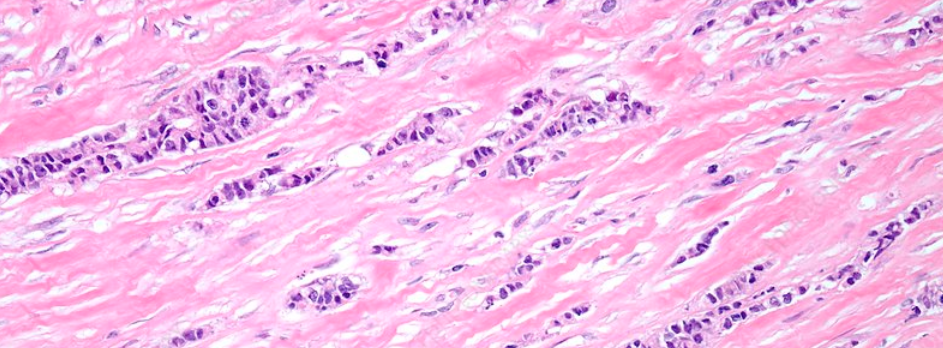

Most lobular tumours lack a protein called E-cadherin, which normally helps cells stick together. The absence of this protein in ILC causes the cancer cells to spread out individually and in thin lines, rather than forming a lump.

Lobular breast cancer cells often grow in thread-like patterns, which can look a bit like a spiderweb. This makes tumours hard to detect by touch or even on scans.

Doctors call this a “loose or diffuse growth pattern“.

There are several subtypes of lobular tumours (e.g. classic, alveolar, solid, tubulolobular, pleomorphic). Sometimes, lobular and NST/ductal cancers occur together – these are called mixed ILC/NST tumours.

Diagnosis typically involves a combination of mammograms, ultrasounds and biopsies, followed by histopathology (microscopic images of the biopsy).

Confirmation of the diagnosis of ILC requires histopathology.